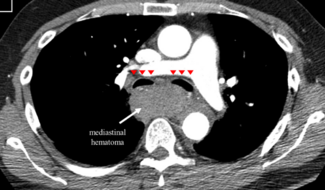

Clinical Images

Bruno Brochado, MD; Andre Alexandre, MD; Tiago Adrega, MD; Joao Silveira, MD; Severo Torres, MD; Les Stewart

A 65-year-old man who presented with lateral ST-segment-elevation myocardial infarction was referred for primary percutaneous coronary intervention. These image show brachiocephalic artery perforation with subsequent mediastinal hematoma.